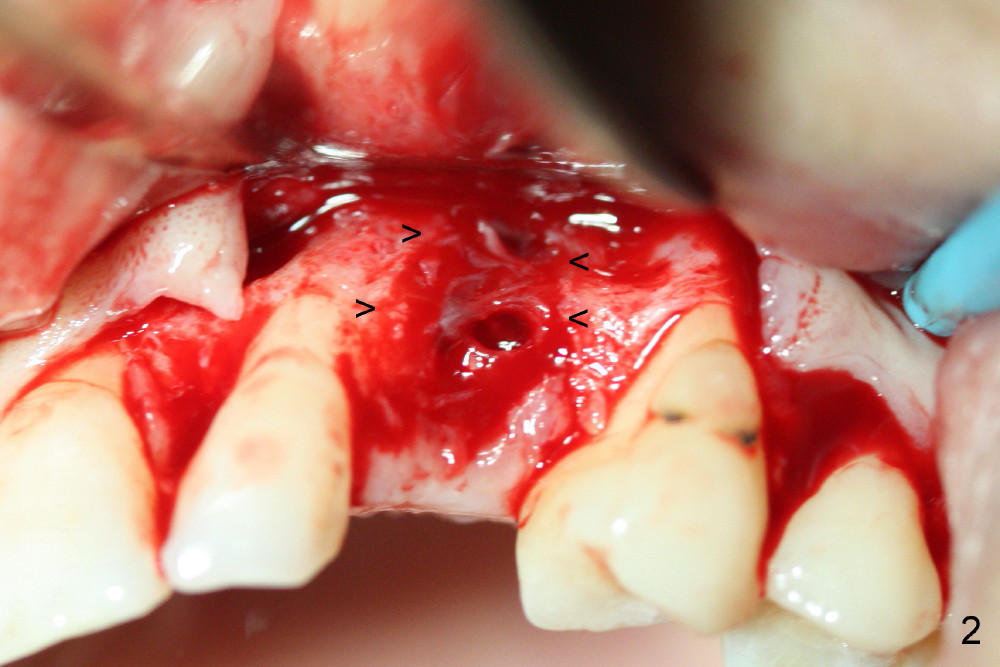

One month post-implantation at the site of the upper left deciduous canine, the patient returns for follow-up with chief complaint "The crown is a little loose. A bubble is becoming smaller". Exam shows an abscess (Fig.1 <) above the provisional (#11). The provisional is loose with mild tenderness. A pull on the provisional leads to dislodgement of the abutment and implant. Raising the buccal flap reveals perforation of the buccal plate with granulation tissue (Fig.2). After debridement (Fig.3), allograft and Osteogen is placed in the defect, followed by Osteotape (Fig.4 *) and suture. This complication can be prevented by CT information. A deciduous tooth socket is small. The immediate implant should be not too large, leaving 2 mm buccal gap. Three months 20 days post graft, the ridge looks not so atrophic (Fig.5). There is no sign of bone resorption (Fig.6). The patient will return for implant placement for the second time soon. Measure the bone width with bone caliper after local anesthesia. Fully expose the alveolus. Start osteotomy as palatal as possible. Repeatedly check osteotomy position and trajectory. Use surgical stent. The implant will not be too long or too wide. Is the ridge as wide as clinically shown?